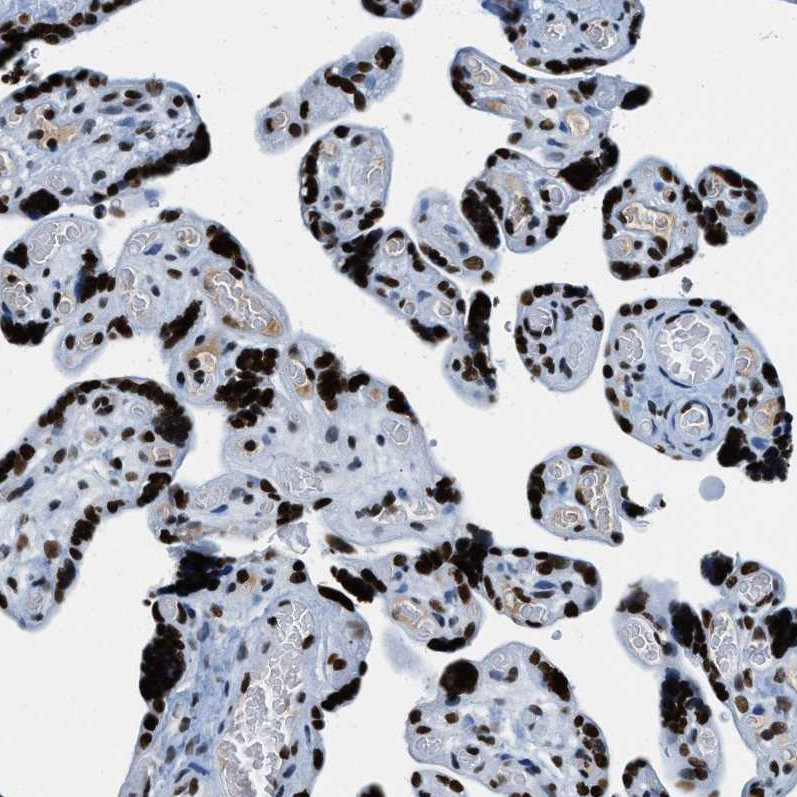

Product information "Anti-TOP1"

Protein function: Releases the supercoiling and torsional tension of DNA introduced during the DNA replication and transcription by transiently cleaving and rejoining one strand of the DNA duplex. Introduces a single-strand break via transesterification at a target site in duplex DNA. The scissile phosphodiester is attacked by the catalytic tyrosine of the enzyme, resulting in the formation of a DNA-(3'-phosphotyrosyl)- enzyme intermediate and the expulsion of a 5'-OH DNA strand. The free DNA strand then rotates around the intact phosphodiester bond on the opposing strand, thus removing DNA supercoils. Finally, in the religation step, the DNA 5'-OH attacks the covalent intermediate to expel the active-site tyrosine and restore the DNA phosphodiester backbone. Regulates the alternative splicing of tissue factor (F3) pre-mRNA in endothelial cells. Involved in the circadian transcription of the core circadian clock component ARNTL/BMAL1 by altering the chromatin structure around the ROR response elements (ROREs) on the ARNTL/BMAL1 promoter. [The UniProt Consortium] Buffer: 40% glycerol and PBS (pH 7.2). 0.02% sodium azide is added as preservative. Highest antigen sequence identity to mouse: 92% and to rat: 93%

| Application: | ICC, IHC, WB |